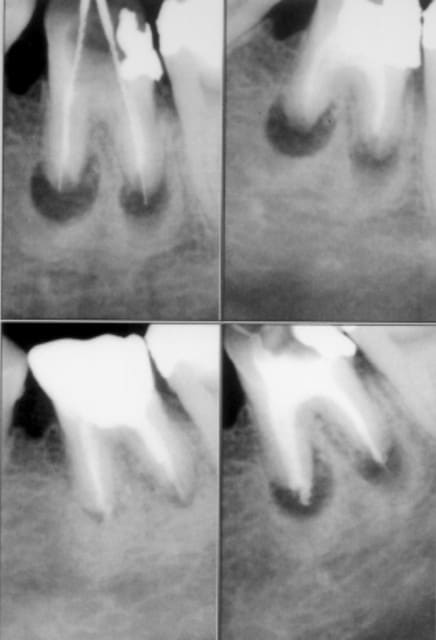

Algi

24/02/2005 à 17h24

ben finalement, sans le flash...

Imgp0525 jvucfx - Eugenol

Imgp0526 vwfhrc - Eugenol

Imgp0527 aclcfh - Eugenol

Ylfwcw979cz1jnx9gfqeaxndiuzk - Eugenol

24/02/2005 à 17h28

Dents traitées y'a maintenant 1 à 4 mois et qui vont bien merci. Avec lentulo+N2 sans formaldéhyde et laser. Ai pas eu de suites lors de tels dépassements même si je me suis posé de sales questions aprés le premier... maintenant j'ai l'habitude.. à croire que les pâtes aux HE directement dans les lesions apicales c'est pas si mal :)

quand même: quelques douleurs "de suite" ça oui mais qui disparaissent en 1/2 heure à 2 heures et parés va bene...